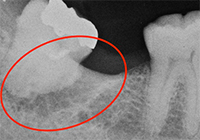

特に大臼歯部において、歯周病の進行に伴う歯槽骨の喪失により、根間部の歯周組織があたかもトンネル状になってしまった状態を”根分岐部病変”と言います。 その部位にはプラークが停滞しやすく、清掃が困難であるため、疲れた時や体調が優れないときなどに、腫れ・排膿・ブラッシング時の疼痛や出血などを繰り返すことがあります。

個々の解剖学的形態や、さまざまな誘発因子が考えられるために、歯周病治療の中でも最も厄介で、抜歯になることも少なくありません。

抜歯した下顎大臼歯です。2つに根が分かれています。

抜歯前にファーケーションプローブで分岐部病変を水平的に診査しているところです。残念ながらIII度でした。

抜歯後に改めてファーケーションプローブを通したところです。骨の喪失状況がわかると思います。